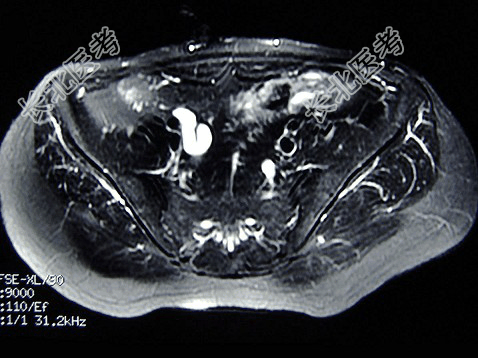

- 多项选择题女,31岁, 右侧腰部胀痛不适,MRI检查如图所示, 下列说法正确的是 ( )

A、右肾重度积水

B、右侧输尿管粗细不均并迂曲扩张

C、右侧输尿管下段呈囊样扩张

D、左肾输尿管未见异常

E、考虑为右侧输尿管囊肿